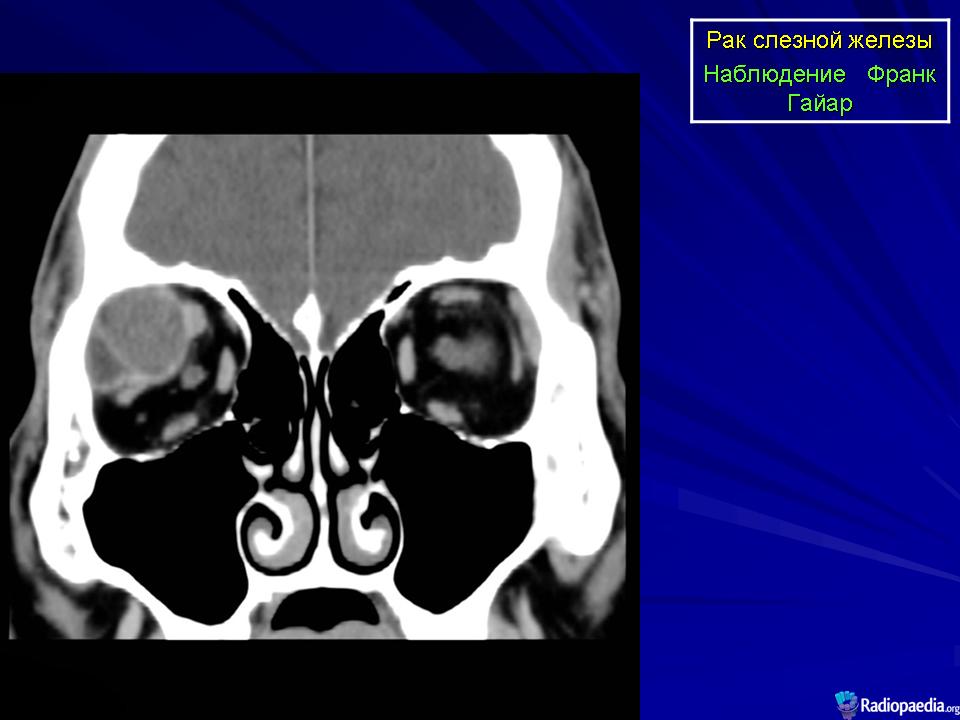

Диагноз устанавливают только после гистологического исследования. Предположительный диагноз может быть установлен на основании анализа клинических симптомов и результатов инструментального исследования. При рентгенографии на фоне увеличенной в размерах орбиты выявляются участки костной деструкции, чаще в верхненаружной, верхней и наружной стенках орбиты. Компьютерная томография позволяет определить протяженность тени опухоли, неравномерность ее краев, распространение в прилежащие экстраокулярные мышцы и неравномерность контуров костной стенки орбиты или ее полное разрушение, а ультразвуковое исследование — лишь наличие тени опухоли и ее плотность. Радиосцинтиграмма орбиты при аденокарциноме характеризуется увеличением коэффициента асимметрии, свойственного злокачественным опухолям. Информативна дистанционная термография, особенно с сахарной нагрузкой. Уточнить диагноз помогает дооперационная тонкоигольная аспирационная биопсия.